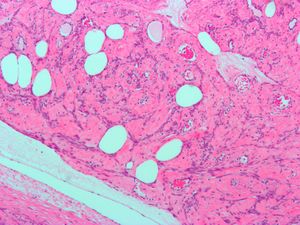

Histopathology of uterine fibroids typically show smooth muscle in a whorled (fascicular) pattern.[36]

This variant of Van Gieson's stain distinguishes muscle (yellow) from connective tissue (red)